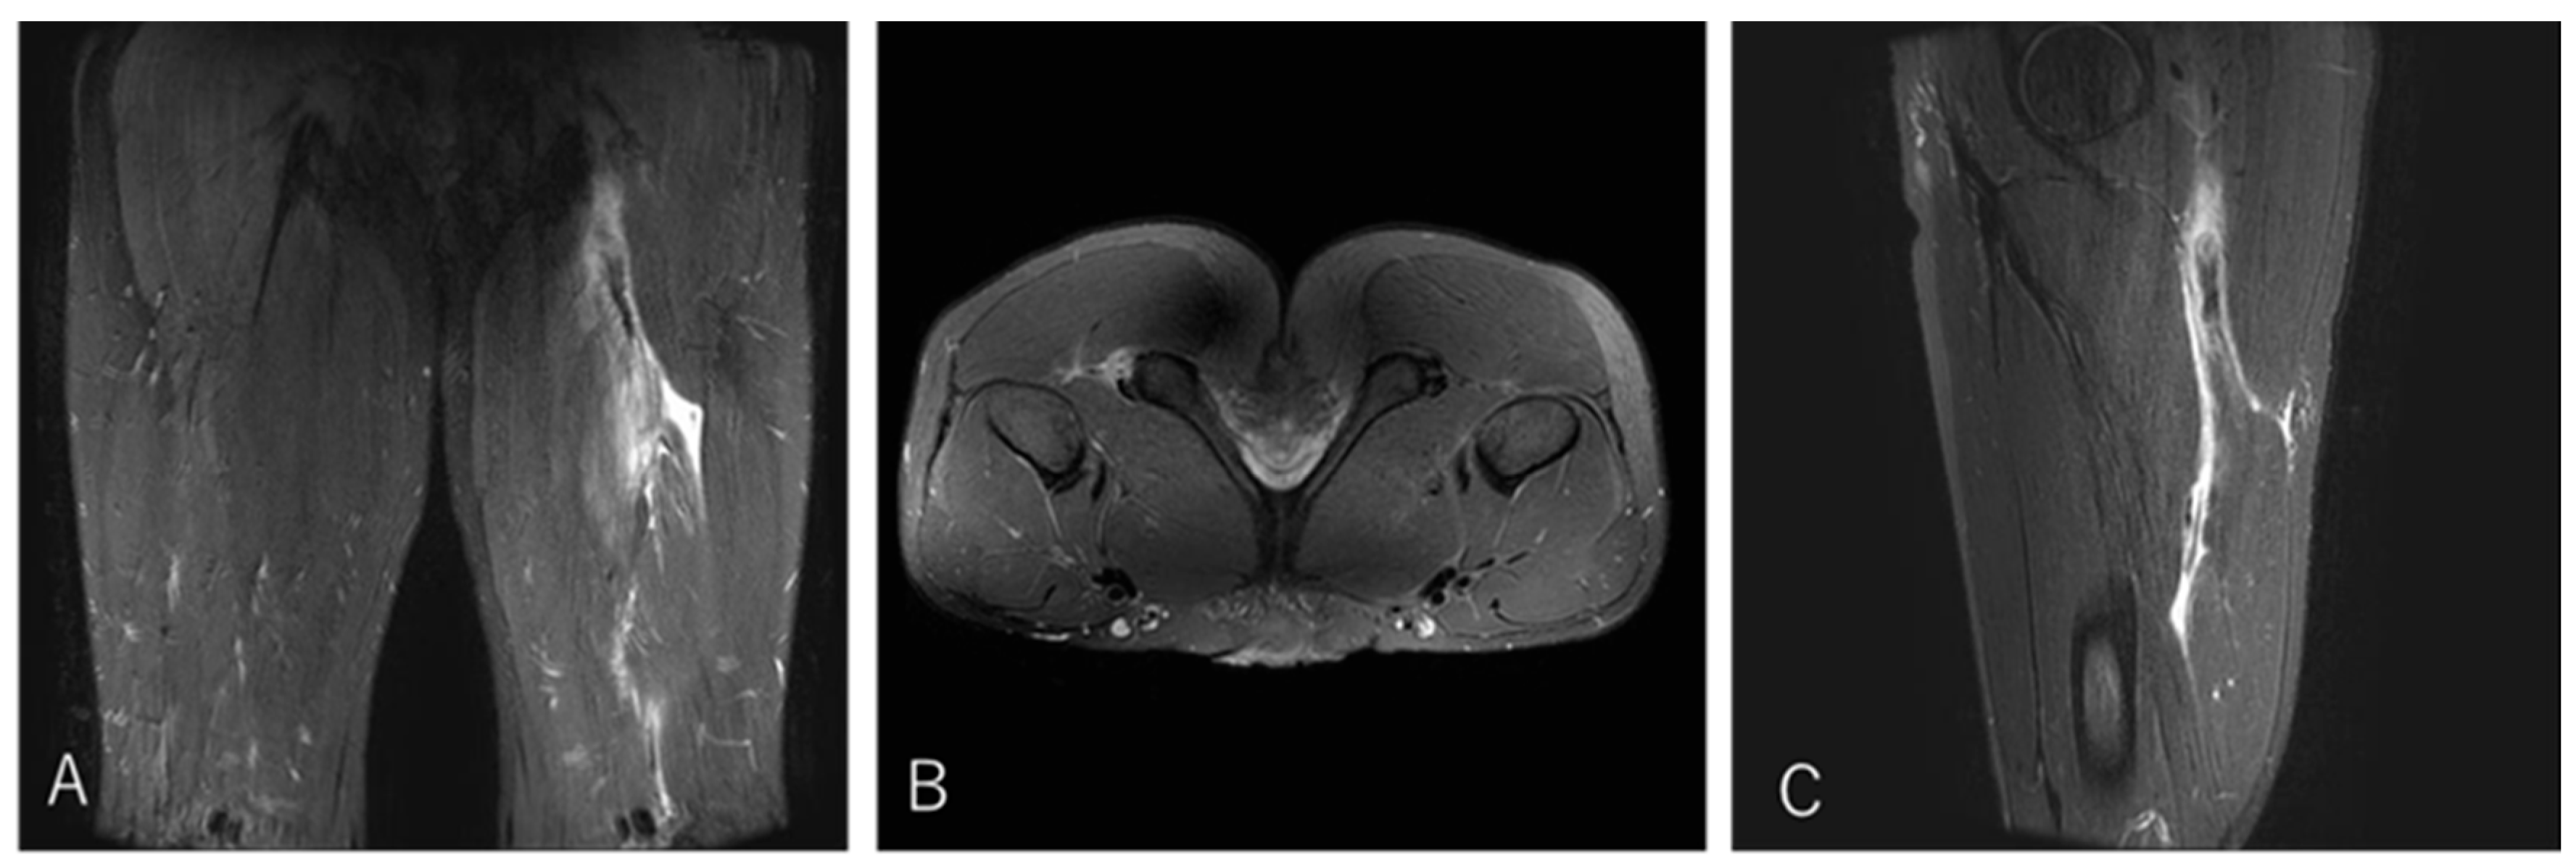

3.4.3. Case 3—Type I/Zone C (MTJ Injury), Grade 2

A 21-year-old scrum half (BK) developed pain in the proximal posterior thigh while changing direction to chase an opposing player. He returned to play after 10 weeks (Figure 6).

Figure 6. Case 3 MRI images: Conjoint tendon MTJ injury, Type I. (A) (Coronal image): The injured area was the proximal MTJ on CT, with haemorrhage observed bilaterally and tortuosity noted on CT. (B) (Axial image): prone position, bleeding is present on both BFLH and ST sides of the CT, and the CT is interrupted at the rupture site. (C) (Sagittal image): The CT is slightly retracted and accompanied by a haematoma.